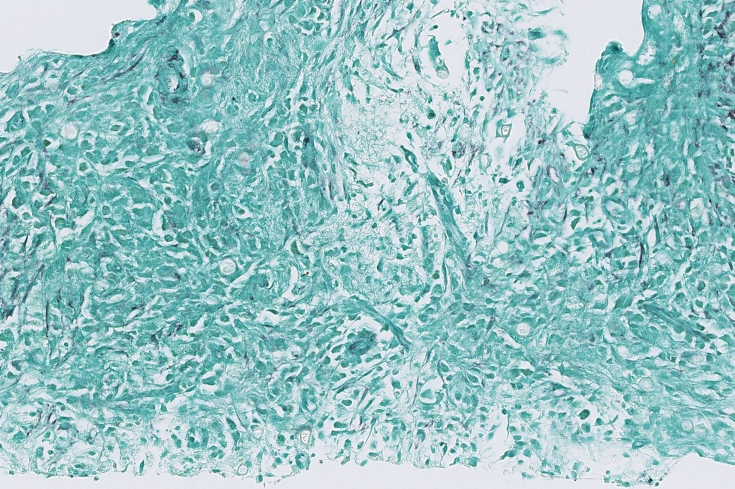

Figure 4. DPAS